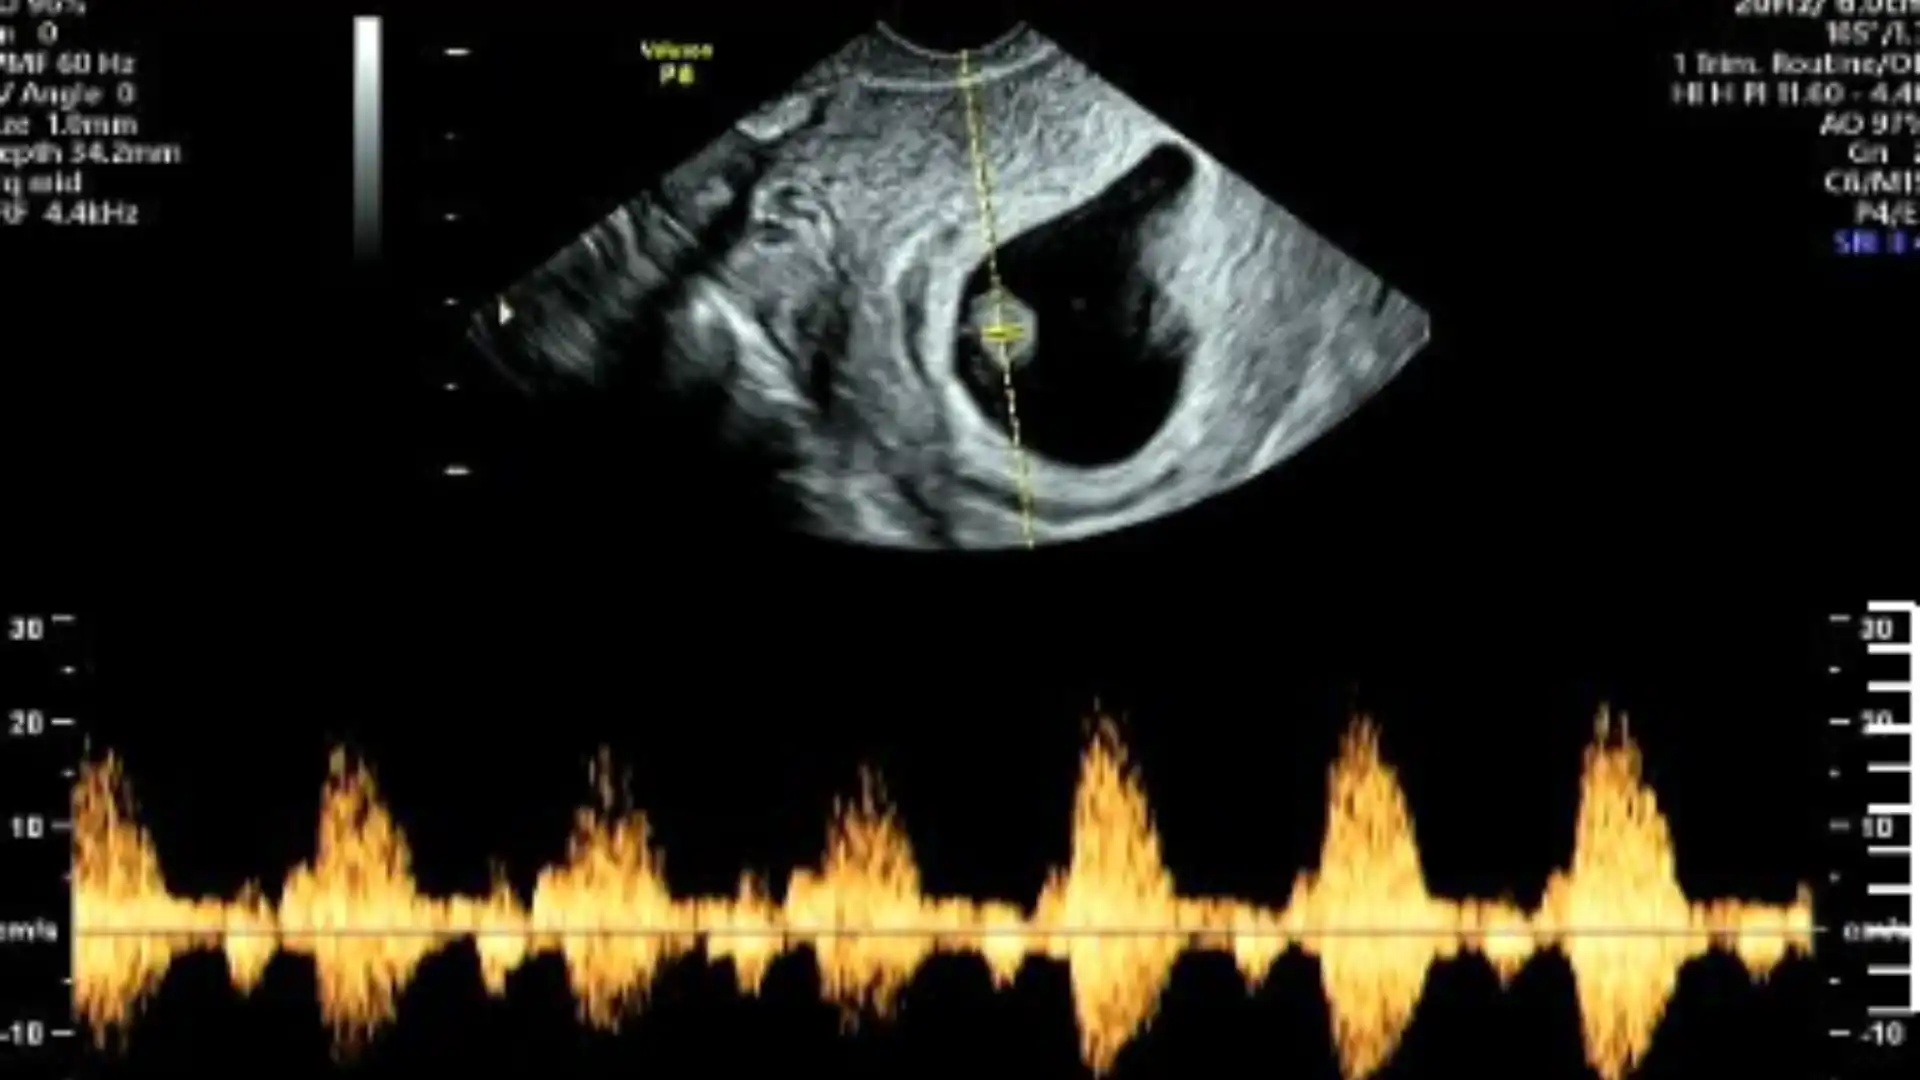

Hình ảnh siêu âm theo dõi: thai trong buồng tử cung phát triển ổn định.

Sau hai tuần điều trị, tình trạng sức khỏe của sản phụ ổn định, thai trong buồng tử cung phát triển tốt. Kết quả này cho thấy hiệu quả của việc chẩn đoán sớm – can thiệp kịp thời – theo dõi sát sao, góp phần bảo đảm an toàn cho người mẹ và duy trì thai trong tử cung.